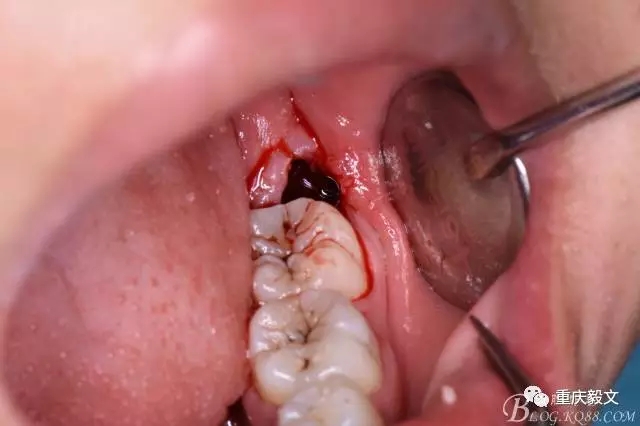

圖7.高速渦輪鉆分牙

圖8.先從頸部橫斷38

圖9.再把38牙冠近遠(yuǎn)中縱斷